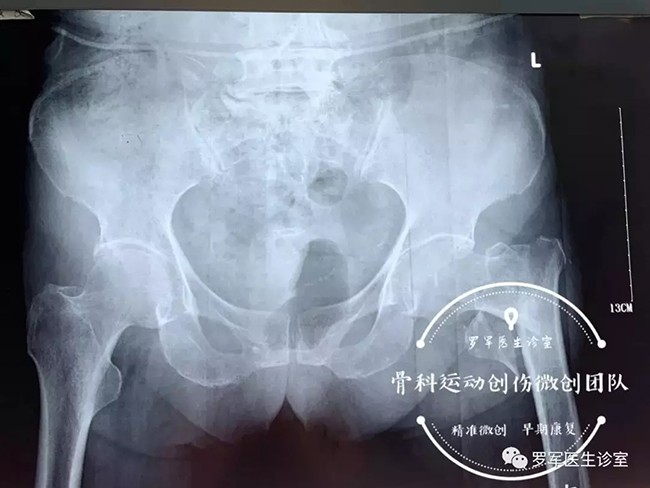

今年86歲高齡的丁奶奶就是其中的一位患者,前不久,丁奶奶走路時不幸摔倒,造成左側(cè)股骨粗隆間粉碎性骨折,被送到廣安醫(yī)院關(guān)節(jié)科救治。

經(jīng)過入院檢查發(fā)現(xiàn)丁奶奶合并有高血壓,糖尿病,動脈粥樣硬化、低蛋白血癥及嚴(yán)重的骨質(zhì)疏松,“無論采取保守治療還是手術(shù)治療,風(fēng)險都很大。但對于高齡老人的骨折,放棄手術(shù)就等于放棄生的希望。”羅軍主任介紹,髖部骨折對高齡、身患各種慢性病的老年人來說無疑是大難題,而且由于骨折后老人臥床至少需要三個月以上,由此引發(fā)的并發(fā)癥,如褥瘡,肺炎、血栓、泌尿系感染等都很容易導(dǎo)致老人死亡。因此,髖部的骨折被稱為老年人“人生的最后一次骨折”。

5月7日,羅軍主任帶領(lǐng)手術(shù)團(tuán)隊按照術(shù)前的討論方案,在C臂機透視下,采用三個微創(chuàng)手術(shù)通道,施行精準(zhǔn)閉合復(fù)位、定位、固定,僅用了大約30分鐘,便成功完成微創(chuàng)內(nèi)固定手術(shù)。手術(shù)進(jìn)行順利,第二天老人就可以在床邊坐起了。老奶奶非常開心,叫家人一定要送面錦旗給醫(yī)生。